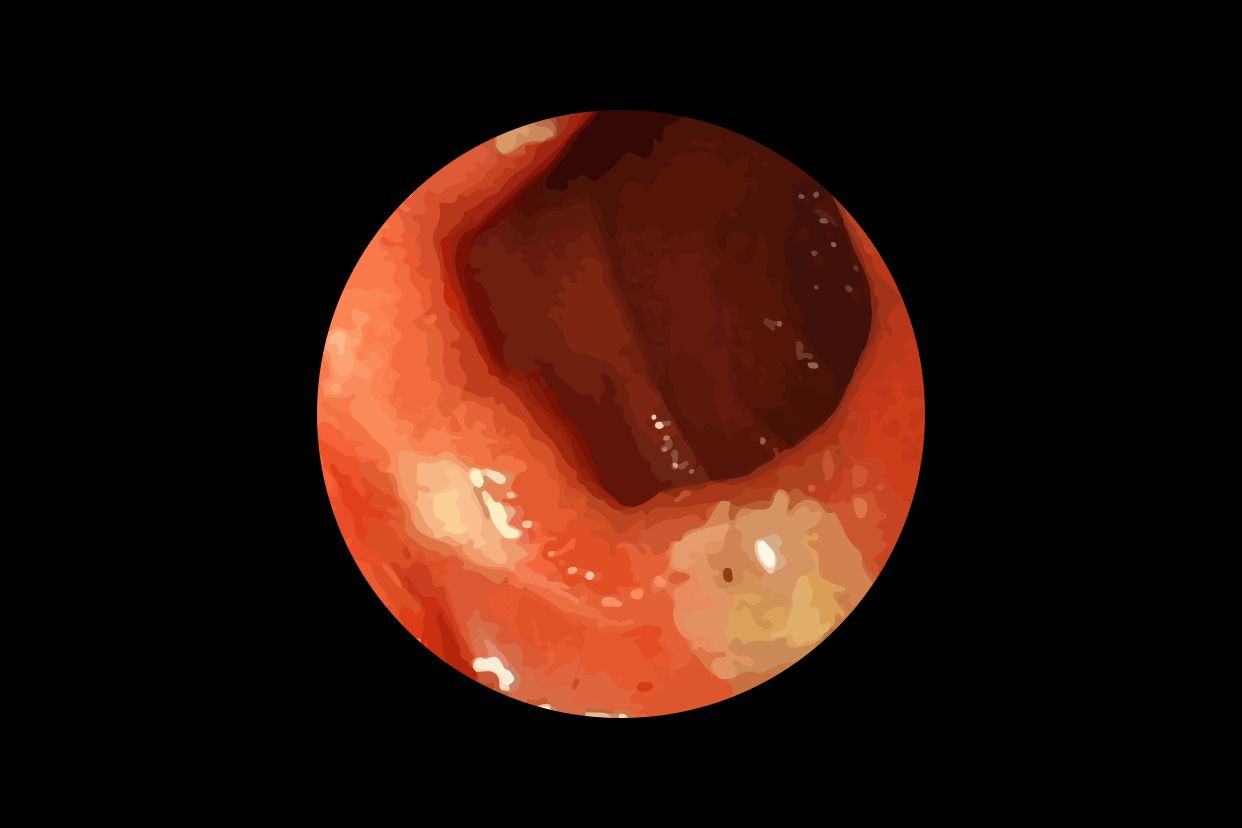

西医在治疗输卵管堵塞时主要采用外科手术,直接切有效。目前可用的手术方法是比较多的,比如当堵塞发生在近端的时候,那么在治输卵管堵塞时可采用COOK导丝复通术、输卵管部分切除再吻合术,手术可再宫腔镜下进行,安全有效且无创治疗女性输卵管堵塞的常见办法有哪些?

输卵管造口术也是治疗输卵管堵塞常见的手术方法,一般来说比较适合梗阻发生在远端的患者治疗输卵管堵塞,而治疗后的妊娠率以及手术的成功率则和输卵管受到破坏的程度有很大的关系,输卵管外部粘连,而内部的纤毛细胞和黏膜皱褶尚且完好的,利用该手术来治输卵管堵塞取得的疗效就非常好。